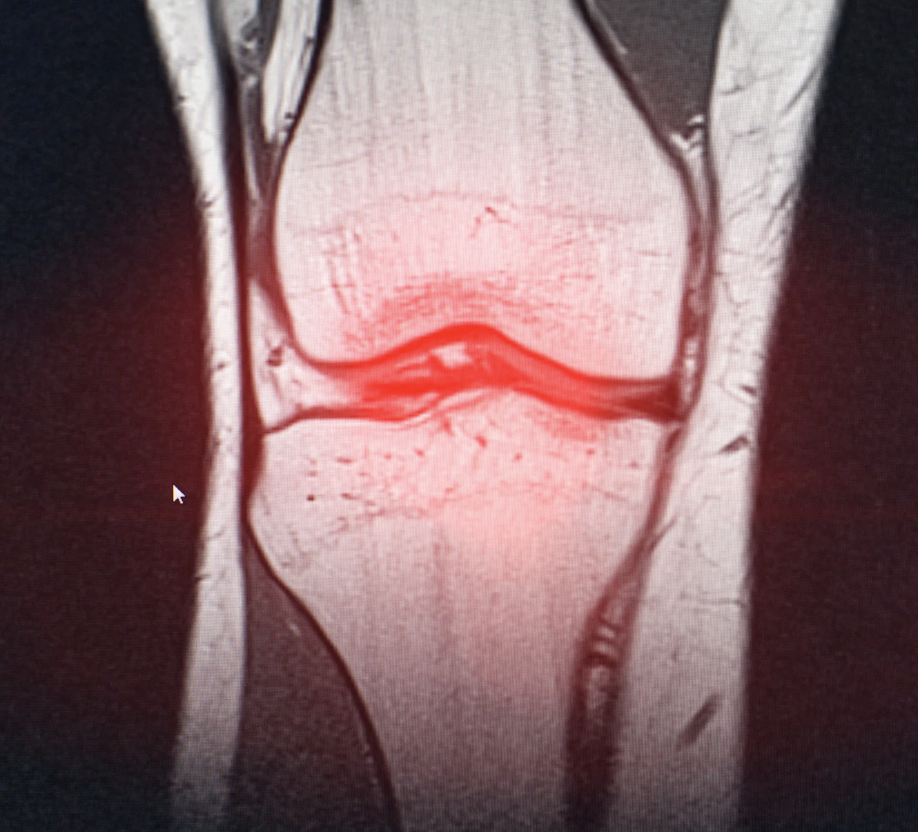

Psoriatic arthritis is mainly diagnosed based on a detailed medical history and physical examination by the doctor. Imaging studies, such as X-rays of the affected joints, may support the diagnosis.

There is no single, definitive blood test for psoriatic arthritis. However, certain laboratory markers, along with imaging tests such as X-rays or CT scans, may help support the diagnosis in some cases.

Yes. Psoriatic arthritis can involve any joint in the body, but the hands, fingers, knees, feet, and toes are commonly affected.